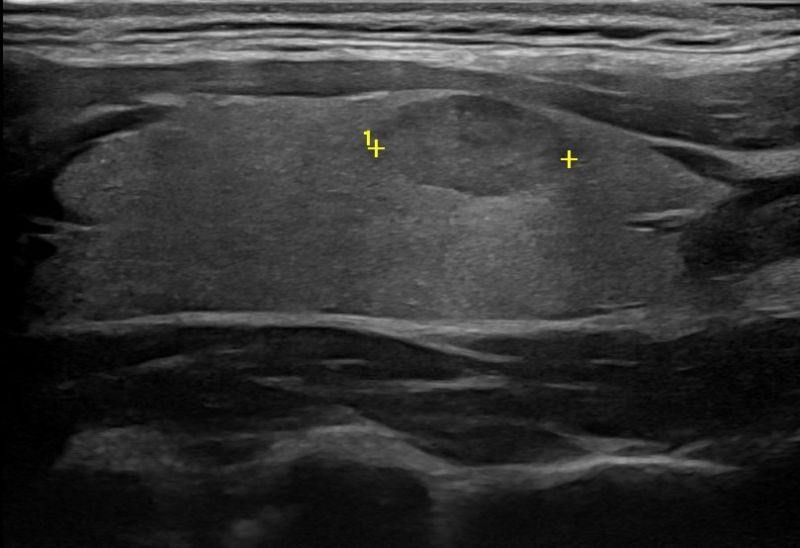

Με την τριπλή μελέτη του Θυρεοειδούς Αδένα, που περιλαμβάνει το B-Μode, το Έγχρωμο Υπερηχογράφημα και την Ελαστογραφία, γίνεται μια ολοκληρωμένη χαρτογράφηση του θυρεοειδούς αδένα. Το περίγραμμα, η αγγείωση και η ελαστικότητα του αδένα, καθώς και η υφή μίας πιθανής βλάβης αξιολογούνται με ακρίβεια και αξιοπιστία.